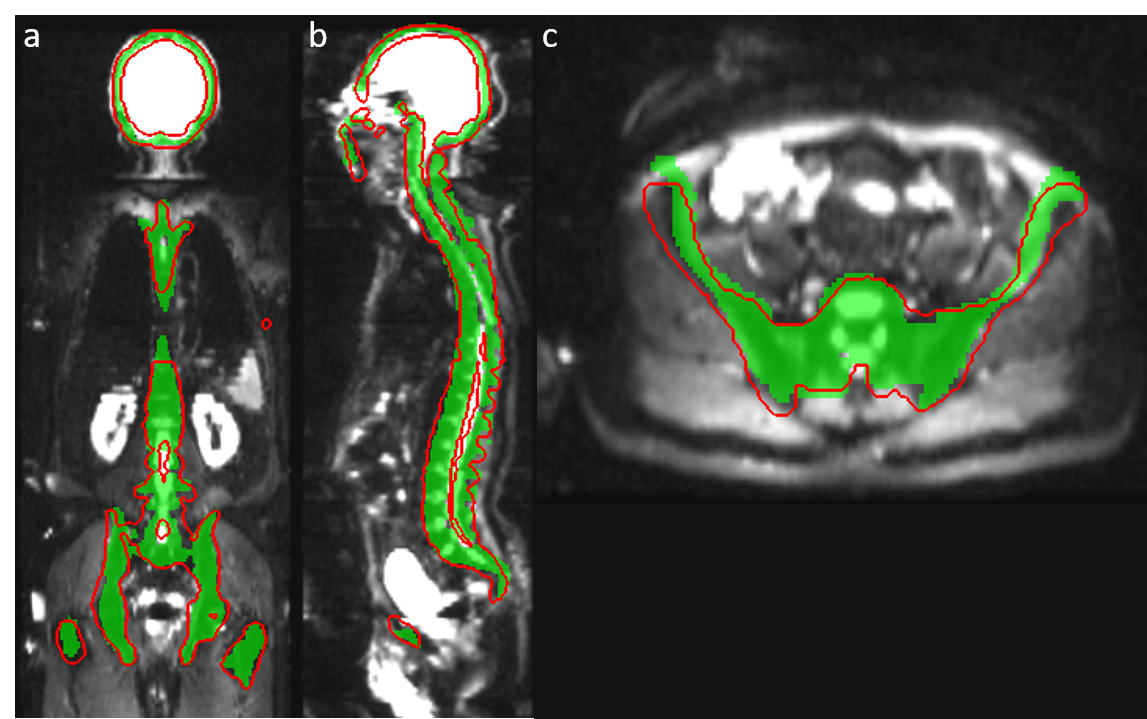

Figure 3: Result of CNN bone segmentation trained on DWI (shown as red contour) using template-based segmentation on T1-weighted images (green mask) as reference.